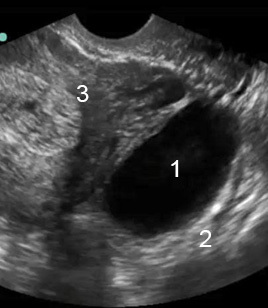

Ovarian Cyst Image

Simple Ovarian Cyst

Acoustic Enhancement

Uterus